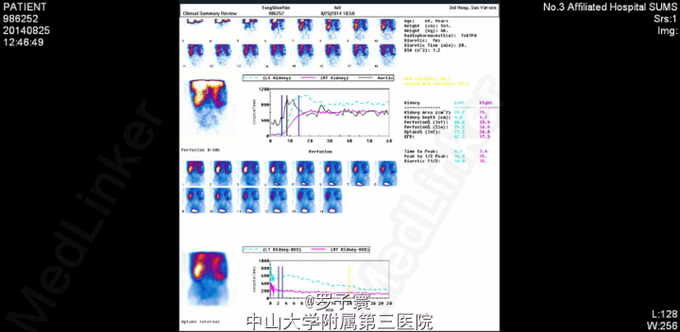

入院完善相关检查:生化:白蛋白34.8g/L。血常规:血红蛋白浓度111g/L。尿常规:潜血+++,白细胞++,亚硝酸盐阳性(+),白细胞计数1049.20个/ul,红细胞计数167.80个/ul。凝血功能、术前筛查、PSA、AFP、CEA、胸片、心电图未见明显异常。双肾CTU,考虑右肾肾癌并淋巴结转移可能性大,彩超腹部大血管提示:腹膜后多发肿大淋巴结,考虑为淋巴结转移Ca可能性大。核素肾动静态显像:1、右肾灌注、功能中度降低;2、左肾灌注,功能正常。